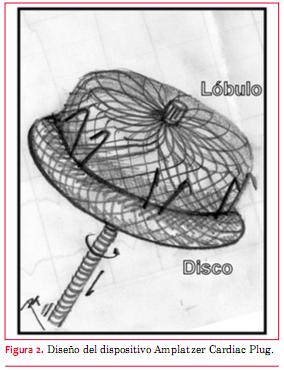

El procedimiento elegido en ambos casos fue el cierre percutáneo endovascular del AAI con dispositivo Amplatzer Cardiac Plug® y se siguió un protocolo similar. Este consiste en un dispositivo autoexpandible de nitinol, con un lóbulo distal y un disco proximal conectados entre sí (figura 2). El nitinol aporta al dispositivo memoria elástica, lo que permite deformar el dispositivo para introducirlo en la vaina que asegura su llegada al AAI, retomando completamente su forma al retirar la vaina una vez alcanzada la ubicación definitiva.